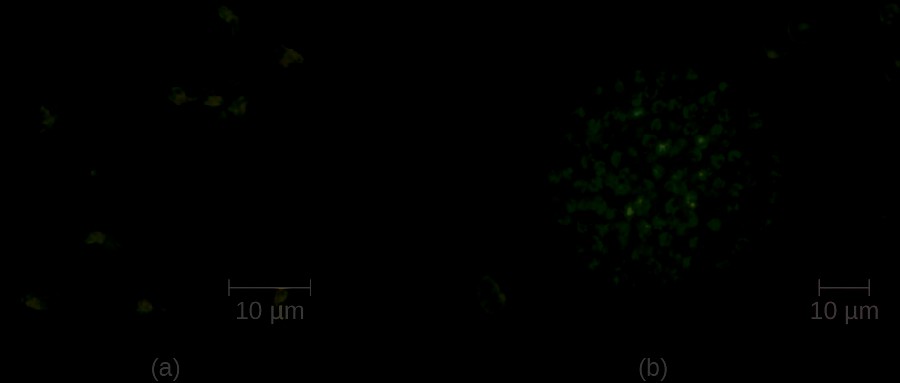

HGA is usually a mild febrile disease that causes flu-like symptoms in immunocompetent patients; however, symptoms are severe enough to require hospitalization in at least 50% of infections and, of those patients, less than 1% will die of HGA.[17] Small mammals such as white-footed mice, chipmunks, and voles have been identified as reservoirs of A. phagocytophilum, which is transmitted by the bite of an Ixodes tick. Five major virulence factors[18] have been reported in Anaplasma; three are adherence factors and two are factors that allow the pathogen to avoid the human immune response. Diagnostic approaches include locating intracellular microcolonies of Anaplasma through microscopic examination of neutrophils or eosinophils stained with Giemsa or Wright stain, PCR for detection of A. phagocytophilum, and serological tests to detect antibody titers against the pathogens. The primary antibiotic used for treatment is doxycycline.

Human monocytotropic ehrlichiosis (HME) is a zoonotic tickborne disease caused by the BSL-2, obligate intracellular pathogen Ehrlichia chaffeensis. Currently, the geographic distribution of HME is primarily the eastern half of the US, with a few cases reported in the West, which corresponds with the known geographic distribution of the primary vector, the lone star tick (Amblyomma americanum). Symptoms of HME are similar to the flu-like symptoms observed in anaplasmosis, but a rash is more common, with 60% of children and less than 30% of adults developing petechial, macula, and maculopapular rashes.[19] Virulence factors allow E. chaffeensis to adhere to and infect monocytes, forming intracellular microcolonies in monocytes that are diagnostic for the HME. Diagnosis of HME can be confirmed with PCR and serologic tests. The first-line treatment for adults and children of all ages with HME is doxycycline.